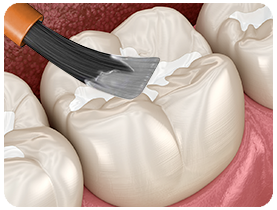

Sealants

Sealants are a revolutionary application that helps protect children’s teeth from decay. All molars have deep grooves on the chewing surface, which can easily trap food, promoting decay. Children start getting their first permanent molars around age six or seven, and by age 13, they have all of their back teeth that need to be sealed.

To “seal” a tooth, a thin, tooth-colored, liquid acrylic coating is applied to the grooves on the surface of the molar and then bonded to the tooth with a high-intensity light. The sealant alters the biting surface of the tooth just enough so that food cannot easily become trapped on the tooth surface, thus protecting the tooth from future decay. The process is simple, painless and takes only a few minutes to perform in our office. We can place sealants on your child’s back permanent teeth as they erupt, usually during their routine cleaning appointment.